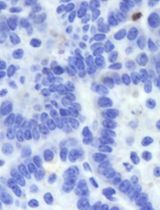

Microwave ablation (MWA) is a thermal ablation technique widely used for local tumor control that has the added potential to stimulate systemic anti-tumor immunity. Although MWA alone rarely eliminates recurrent or metastatic disease, its ability to remodel the tumor microenvironment makes it a promising partner for adoptive cell therapies such as chimeric antigen receptor (CAR)-T cells. However, reproducible protocols for combining these approaches remain limited. This protocol describes the integration of MWA with CAR-T therapy in tumor-bearing mouse models. Human hepatocellular carcinoma cell lines (Hep3B and SK-HEP-1) are inoculated subcutaneously into NOG mice to establish tumors. Localized MWA is performed at adjustable power and duration to induce partial or complete ablation. At defined intervals following MWA, CAR-T cells derived from healthy donor T cells and transduced with a lentiviral vector are injected intravenously. This experimental design uniquely separates MWA and CAR-T delivery, enabling precise evaluation of thermal preconditioning effects on the tumor microenvironment and subsequent CAR-T activity. By combining localized ablation with adoptive immunotherapy, the protocol provides a translationally relevant platform to optimize treatment timing, enhance CAR-T efficacy in solid tumors, and address key barriers in tumor immunology and cancer therapy.

Beyond its local cytotoxic effect, MWA has been shown to elicit an immune-mediated systemic response known as the abscopal effect. This phenomenon describes the regression of metastatic tumors at sites distant from the ablation, driven by immune activation resulting from post-MWA release of cytokines, chemokines, and neoantigens [8–13]. However, the abscopal effect alone is generally insufficient to eliminate secondary tumor sites completely [1,14]. Additionally, the high rate of tumor recurrence following MWA suggests that it may not be adequate as a standalone therapy for metastatic disease. Recent studies have shown that the immunostimulatory effects of MWA can complement immunotherapies such as chimeric antigen receptor (CAR)-T-cell therapy [15,16]. In particular, xenograft models of non-small cell lung cancer have demonstrated enhanced tumor regression when MWA is combined with CAR-T treatment [15,16]. This combination strategy has the potential to address both local and distant tumor sites more effectively than either modality alone.